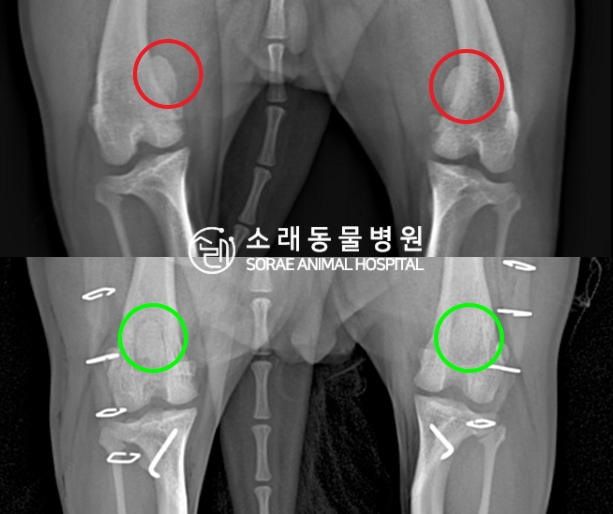

수술전과 수술후에 촬영한 네모의 슬개골

방사선 사진입니다. 나란히 놓고 비교해보니

슬개골의 위치에 확연한 차이가 있는 것을

확인해 볼 수 있는데요. 내측으로 탈구되어 있던

슬개골이 원래 제자리인 활차구에 예쁘게

자리 잡고 있는 모습을 확인할 수 있었습니다.